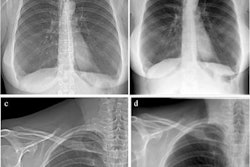

Dark-field CT reconstruction of a clinical chest phantom. Besides conventional attenuation contrast, dark-field contrast is also retrieved, providing information on the porosity of tissue. Here, the chest phantom is filled with a foam insert that simulates lung tissue, and tubes containing different materials (left-to-right: POM, air, powdered sugar, water). While purpose structures are too small and have low conventional attenuation CT, they are easily visible in the dark-field image. Image and caption courtesy of Manuel Viermetz.The group found that the device was effective in capturing dark-field data (i.e., small-angle scattering), which "provides additional valuable diagnostic information on otherwise unresolved tissue microstructure," it noted.